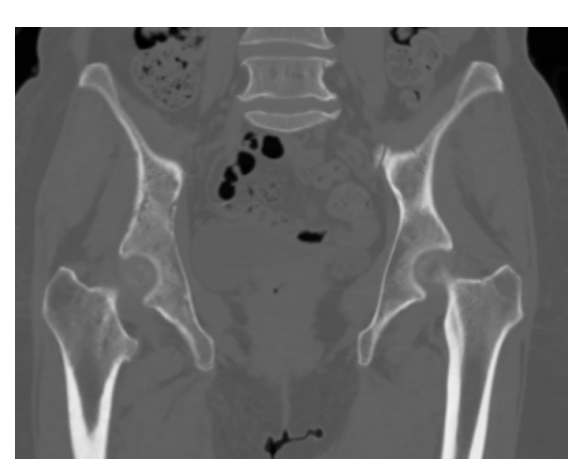

图4 右侧髂骨肿瘤,CT冠状面视图